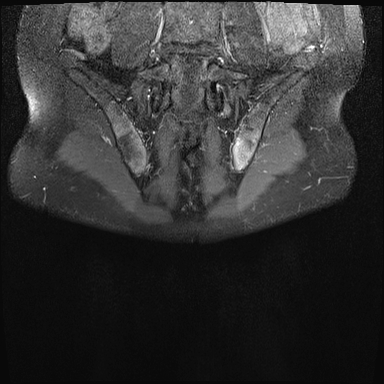

MRI

MRI chuỗi xung T1W sau tiêm thuốc tương phản từ của cùng bệnh nhân cho thấy bờ khớp cùng chậu không đều do bào mòn.

Có ngấm thuốc ở xương dưới sụn và phù nề tủy xương.

Không có tràn dịch khớp.

Thuốc tương phản từ tiêm tĩnh mạch không nhất thiết phải sử dụng để chẩn đoán viêm khớp cùng chậu.

Cuộn qua các hình ảnh MRI và so sánh với các dấu hiệu trên X-quang (hình ảnh cuối cùng).